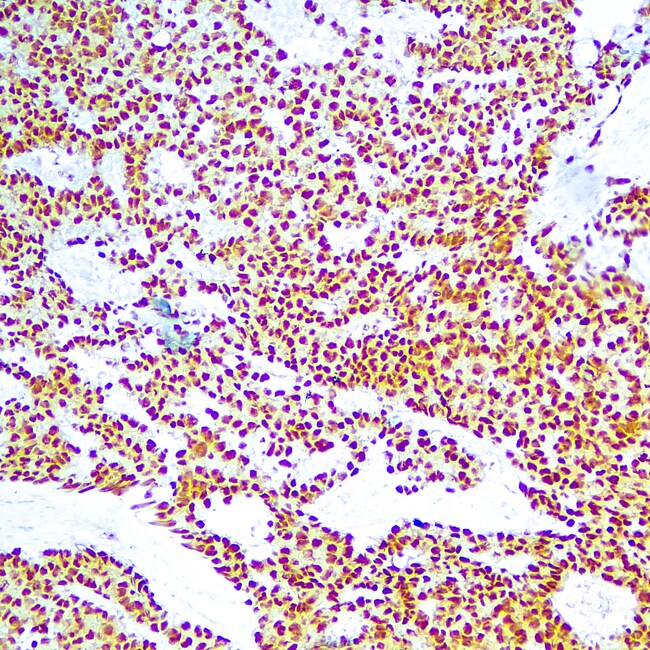

Diagnostic Biosystems OCT 3/4 OCT-3/4 (OCT4/6847R)

OCT-3/4 (also known as POU5F1) is a transcription factor that has been recognized as fundamental in the maintenance of pluripotency in embryonic stem cells and primordial germ cells. It has been proposed as a useful marker for germ cell tumors (GCT) that exhibit features of pluripotentiality (seminoma/dysgerminoma, germinoma and embryonal carcinoma. OCT-3/4 immunostaining has been shown to be sensitive and specific for GCT, whether in primary gonadal or extragonadal sites or in metastatic lesions.